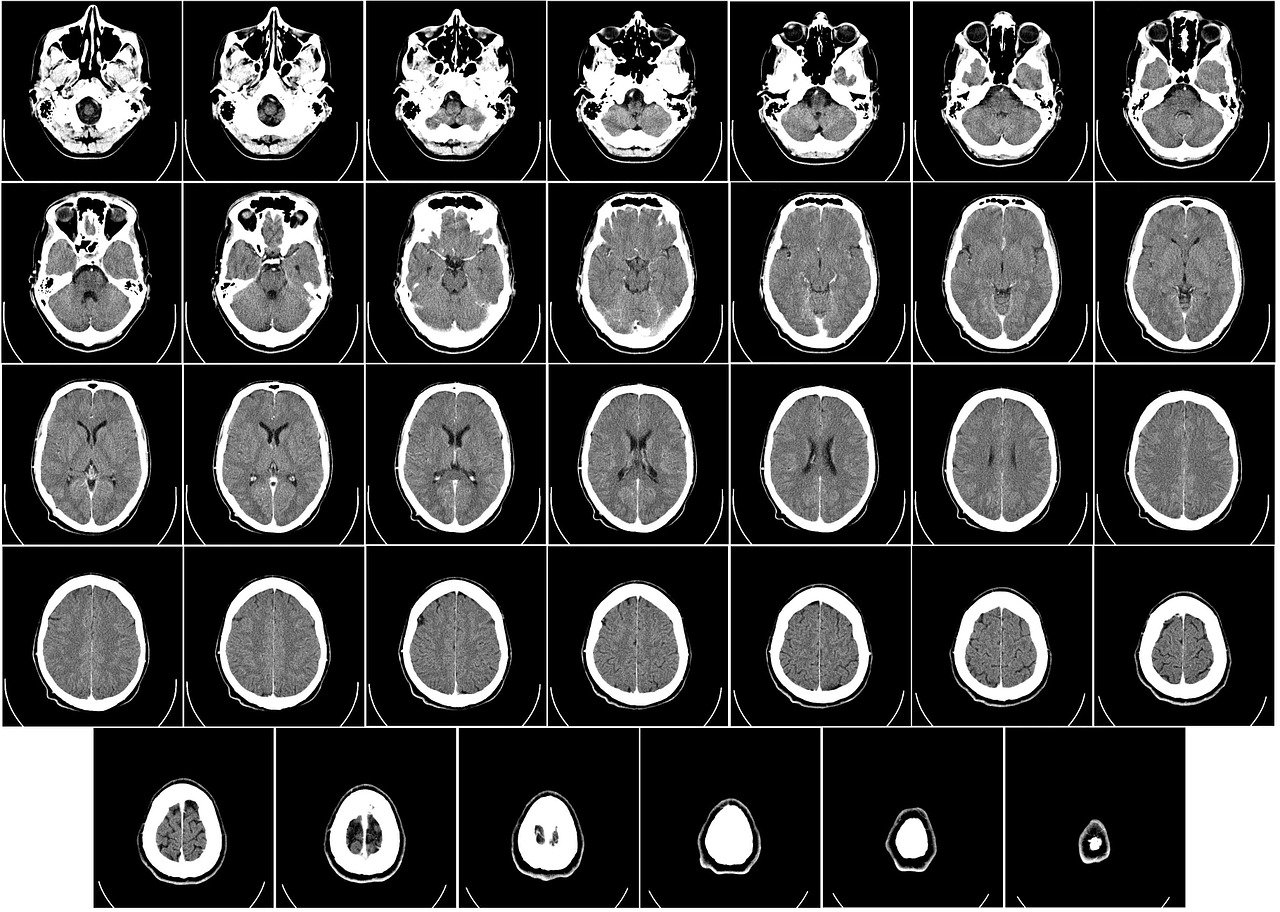

머리의 강 cavity of head에 대해 알아보겠습니다.

두개골은 윗부분은 뇌를 담은 커다란 두개강 cranial cavity로 되어 있고, 두개강 아래에는 안구를 담은 눈오목(안와) optic fovea 사이에 넓은 비강 nasal cavity가 있습니다. 또한 비강을 감싼 뼈의 속 부분에는 부비동 paranasal sinus라 일컫는 공간이 있는데 모두 비강과 연결되어 있습니다.

두개강 cranial cavity, 눈오목(안와) optic fovea, 비강 nasal cavity, 부비동 paranasal sinus, 유달동과 유돌벌집 mastoid sinus and mastoid air cell로 구분할 수 있습니다.

두개강 cranial cavity

뇌두개골( 전두골 frontal bone, 두정골 parietal bone, 후두골 occipital bone, 측두골 temporal bone, 접형골 sphenoid bone, 사골 ethmoid bone)에 감싸인 넓은 강 cavity입니다.

아랫면은 앞, 중간, 뒤의 3개 두 개 우묵을 형성합니다. 3개의 두 개우묵은 앞에서 뒤로 차례로 깊어져 있고 각 두 개 우묵(두 개와) cranial fossa는 아래와 같은 뼈로 이루어져 있다.

앞도 개 우묵(전두개와) anterior cranial fossa : 전두골의 눈 오목(안와) optic fovea, 사골의 사판 cribriform plate, 접형골의 작은 날개(접형 골소 익) lesser wing으로 구성되며, 이곳에는 전두엽 frontal lobe이 이 강 내에 위치합니다.

중 간두 개 우묵(중 두 개와) middle cranial fossa : 접형골의 큰 날개(접형골대익) ala major, 측두골의 비늘(측두골의 인부) squama 부분과 암석위면(암양부상면) superior petrous part로 구성되어 있는데 측두엽 temporal lobe는 이곳에 있습니다.

뒤 두 개 우묵(후두개와) posterior cranial fossa : 측두골 temporal bone의 암석뒤면(암양부후면) posterior petrous portion의 후두골의 후두엽 occipital lobe와 소뇌 cerebellum을 담습니다.

접형골의 큰 날개는 엷고 편평하며, 신경과 혈관을 통하게 하기 위한 작은 구멍이 많습니다. 또한 측두골의 암석 부분도 중이와 내이를 담고 또, 손목(내경) 동맥과 안명신경을 지나가게 하기 위해 속 부분에는 강 cavity가 많습니다.

따라서 중 두 개우묵이 가장 파괴되기 쉽습니다. 이른바 '뇌 저 골절'의 대부분은 중 간두 개우묵에서 일어납니다.